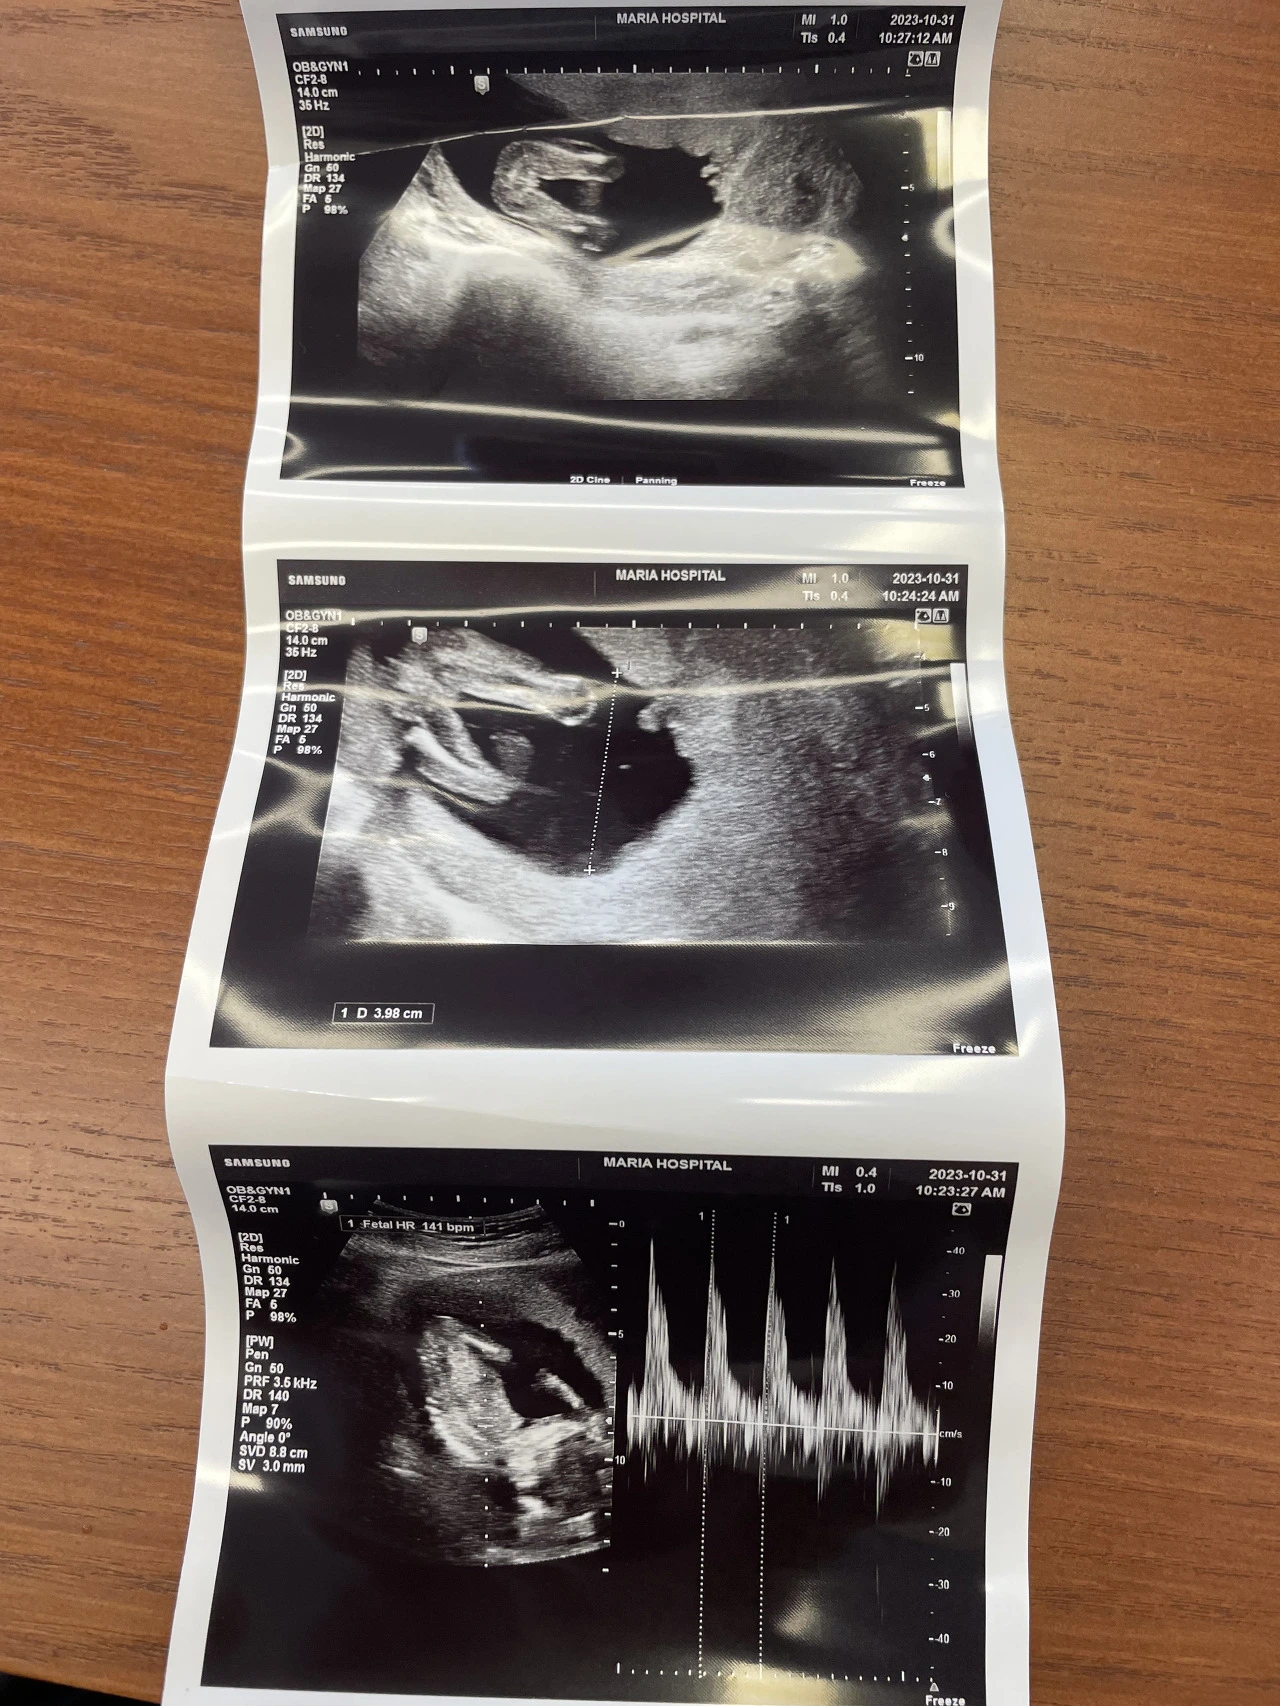

초음파 상에서 콩알만하던 아기가 1.7키로가 됐다.